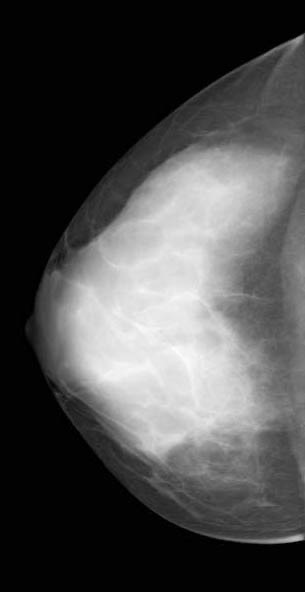

◂Breast Anatomy